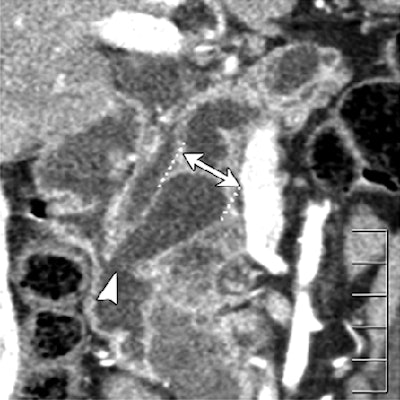

| Dilatation of main pancreatic duct (MPD) in intraductal papillary mucinous neoplasms of the pancreas (IPMN). Oblique coronal reformatted images were generated from pancreatic phase scanning, with 5-cm scale at lower right on each image. Above, adenoma; below, noninvasive carcinoma; bottom, invasive carcinoma. As the maximum diameter of the MPD (arrows indicate distance between dotted lines) increased by 3.8 mm (top), 21.4 mm (below), and 40.9 mm (bottom), the likelihood of malignancy of IPMN increased. Arrowhead on image below indicates protrusion of dilated MPD, showing water attenuation into the ampulla of Vater. Many mural nodules are seen in dilated MPD in invasive carcinoma on bottom image. |

The following findings showed significant differences among the three groups: maximum diameter of the main pancreatic duct (MPD), size (length of major axis) of the largest mural nodule in the MPD or in any associated cystic lesion, abnormal attenuating area in the surrounding parenchyma, calcification in the lesion, protrusion of the MPD into the ampulla of Vater, and bile duct dilatation, the authors reported.

"Of seven findings that were significant predictors of invasion in the univariate analysis, the following two findings remained significant in the multivariate analysis: presence of a mural nodule in the MPD of 6.3 mm or larger, and presence of an abnormal attenuating area in the surrounding parenchyma," the authors wrote.

When tumors meeting one or both of these criteria were identified as invasive, CT's sensitivity, specificity, and accuracy for detecting parenchymal invasion were 90%, 88%, and 89%, respectively.